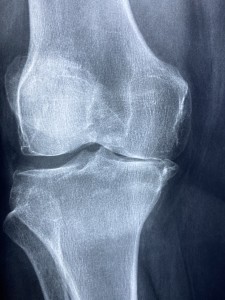

Arthritis: Entzündungen schaden der Kognition (Foto: pixabay.com, Dr. Manuel Gonzalez Reyes) |